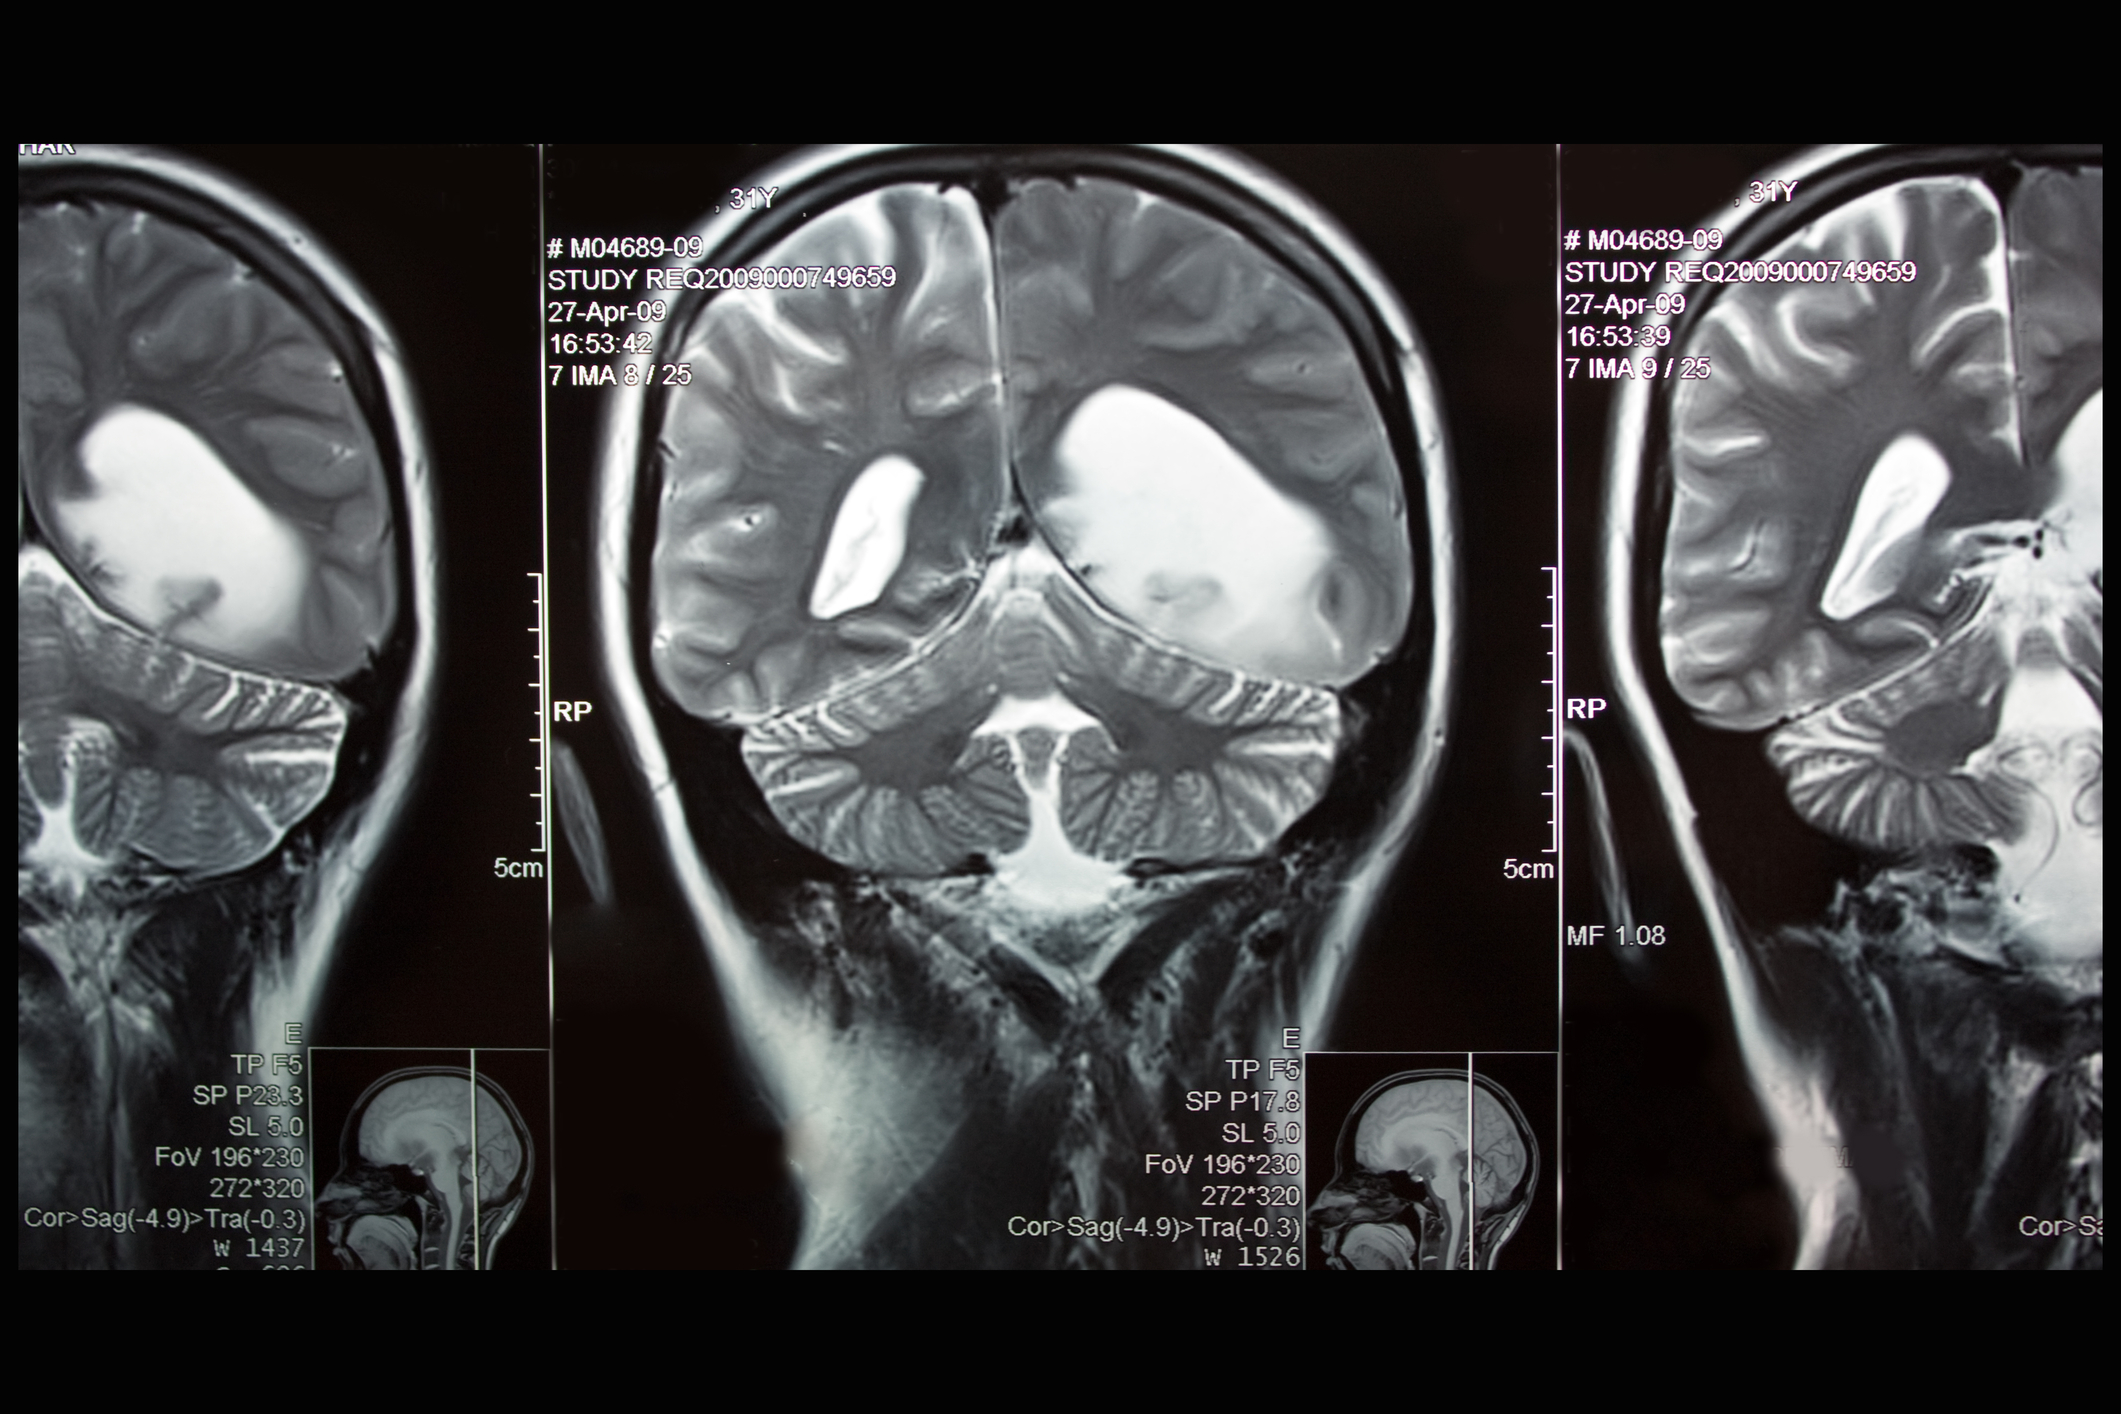

Dear Eric: A year ago, I had to have a procedure for a brain tumor. A very scary emotional roller coaster event. My best friend of 42 years, said, “Don’t worry; I will be with you every step of the way.”